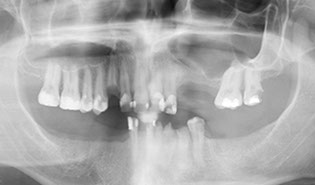

Your diagnosis includes a thorough radiographic examination. Brener Clinic takes 3D Cone Beam CT Scans as well as digital impressions of your upper and lower jaws to assist with treatment planning. A thorough medical history is also taken so we can communicate with your doctor and specialist medical team if necessary.